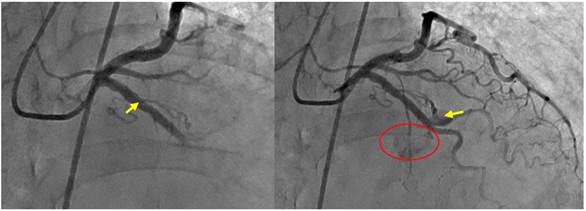

- arteriografía coronaria que evidencia tronco coronario común corto sin lesiones, ADA de mediano calibre y largo recorrido hasta ápex sin lesiones significativas. Se visualizó una fistula coronario-pulmonar en segmento medio de ADA (Figura 1). La ACD de buen calibre sin lesiones, observando una fístula hacia arteria pulmonar en su segmento proximal (Figura 2). En ninguno de los dos casos, se encontró alteración del flujo coronario de forma distal. La arteria circunfleja de buen calibre, sin lesiones. Dichos hallazgos posiblemente sean de origen congénito sin repercusión hemodinámica y que no estaban en relación a la sintomatología de paciente.

Figura 1: A) Arteriografía a ADA y circunfleja. Se visualiza el inicio (flecha) de la fístula desde segmento medio de ADA. B) Se visualiza porción final de la fístula (flecha) y contraste en arteria pulmonar (círculo rojo).